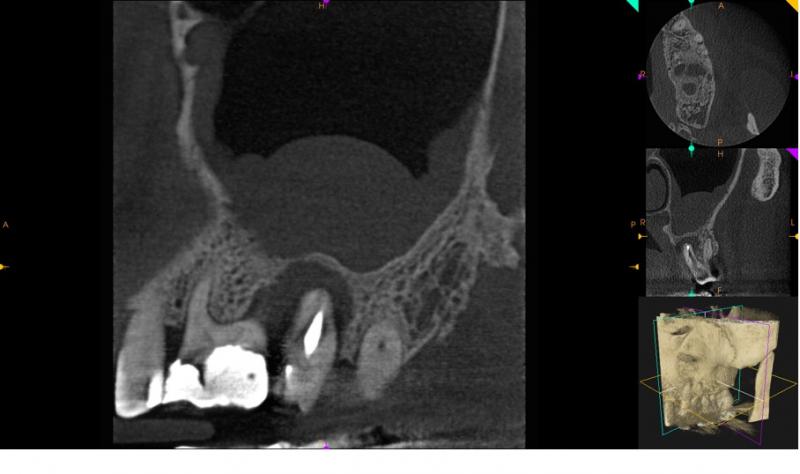

Tomografia szczęka, okolica 27.

Zatoka szczękowa lewa zmieniona patologicznie. Zatoka niepowietrzna w około 1 swojej objętości.

Ciągłość dna zatoki szczękowej zachowana.

Ząb 26 – przeleczony kanałowo. Wypełnione trzy kanały. Kanał podniebienny wypełniony na całej swojej długości. W kanałach policzkowych w części przywierzchołkowej materiał wypełniający niewidoczny (mezialny – 2,5mm, dystalny – 1,5mm). Kształt korzenia mezialnego oraz przejaśnienie znajdujące się w kierunku podniebiennym od kanału mezialnego może sugerować obecność kanału dodatkowego. W okolicy okołowierzchołkowej korzenia mezialnego widoczne ognisko rozrzedzenia struktury kostnej o średnicy 1,5mm x 2,5mm.

Ząb 27 – przeleczony kanałowo. Wypełniony kanał podniebienny. Kanały policzkowe niewypełnione. W korzeniu mezialnym materiał wypełniający widoczny w policzkowo od naturalnego światła kanału (via falsa).

W korzeniu podniebiennym widoczne radiologiczne przejaśnienie mogące odpowiadać szczelinie złamania.

Wokół korzeni widoczne rozległe ognisko rozrzedzenia struktury kostnej obejmujące całą długość korzeni mezialnego i podniebiennego.

Zmiana powoduje przerwanie ciągłości blaszki zbitej kości szczęki od strony podniebiennej.